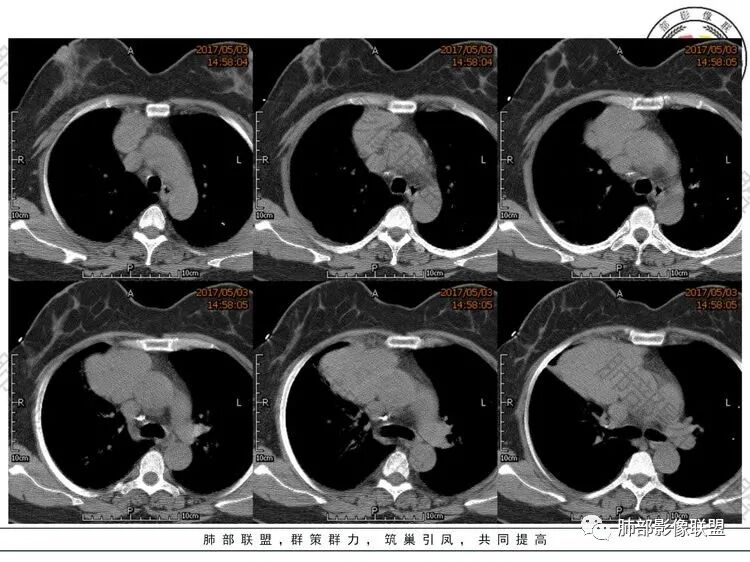

中年女性,体检发现,纵隔前外侧见不规则肿块,内见散在钙化灶,主动脉及心脏受压向后内侧轻度移位,增强后呈均匀性强化,未见明显坏死区,肺动脉延伸其中,轮廓光滑,肿块前外侧见胸膜尾。考虑胸膜来源可能性大,SFT?鉴别胸腺瘤

中年女性,体检,相邻肺组织受压,大部位于右前纵膈,貌似右侧内乳动脉增粗,肿物定位前纵膈,边界清晰,内见线样分隔及钙化,强化均匀!考虑胸腺瘤!

晨读:定位前纵隔偏右侧,病变向右侧突出,形态欠规则,与肺组织交界清楚,右肺受压体积缩小,平扫密度不均匀,可见高密度钙化,增强后可见条状强化,51岁,考虑胸腺瘤囊变,囊性畸胎瘤,鞘瘤囊变

晨读:中年女性,体检发现病变。胸部CT:纵隔右前外侧不规则肿块,内乳动脉供血、胸膜掀起,肺动脉似乎也伸入其中?主动脉及心包受压向内后侧移位,肿块分叶、内见明显分隔、散在点状钙化灶,增强后呈均匀性强化。左侧膈顶有抬高?考虑:胸腺瘤(还是选B2吧)?鉴别SFT、神经源性肿瘤、淋巴瘤等。

晨读,中年女性,右侧纵膈团块状软组织肿块,边缘膨隆分叶,内可见点状钙化,增强后均匀强化,常规考虑胸腺瘤,鉴别胸膜来源SFT

晨读,老年女性,右前纵隔、心包旁软组织密度影,内有斑点状钙化,周围脂肪间隙清晰,增强均匀强化,可见线样血管影,走行尚自然,考虑胸腺瘤,鉴别淋巴瘤、SFT

右前纵隔肿块,分叶,密度均匀,见钙化,均匀强化,血管走行自然,考虑胸腺瘤,鉴别淋巴瘤。

晨读:老年女性,右前纵隔分叶状软组织密度肿块影,内有斑点状钙化,周围脂肪间隙清晰,增强轻度均匀强化,可见线样血管穿行影。常规考虑胸腺瘤(AB型),鉴别淋巴瘤、SFT。